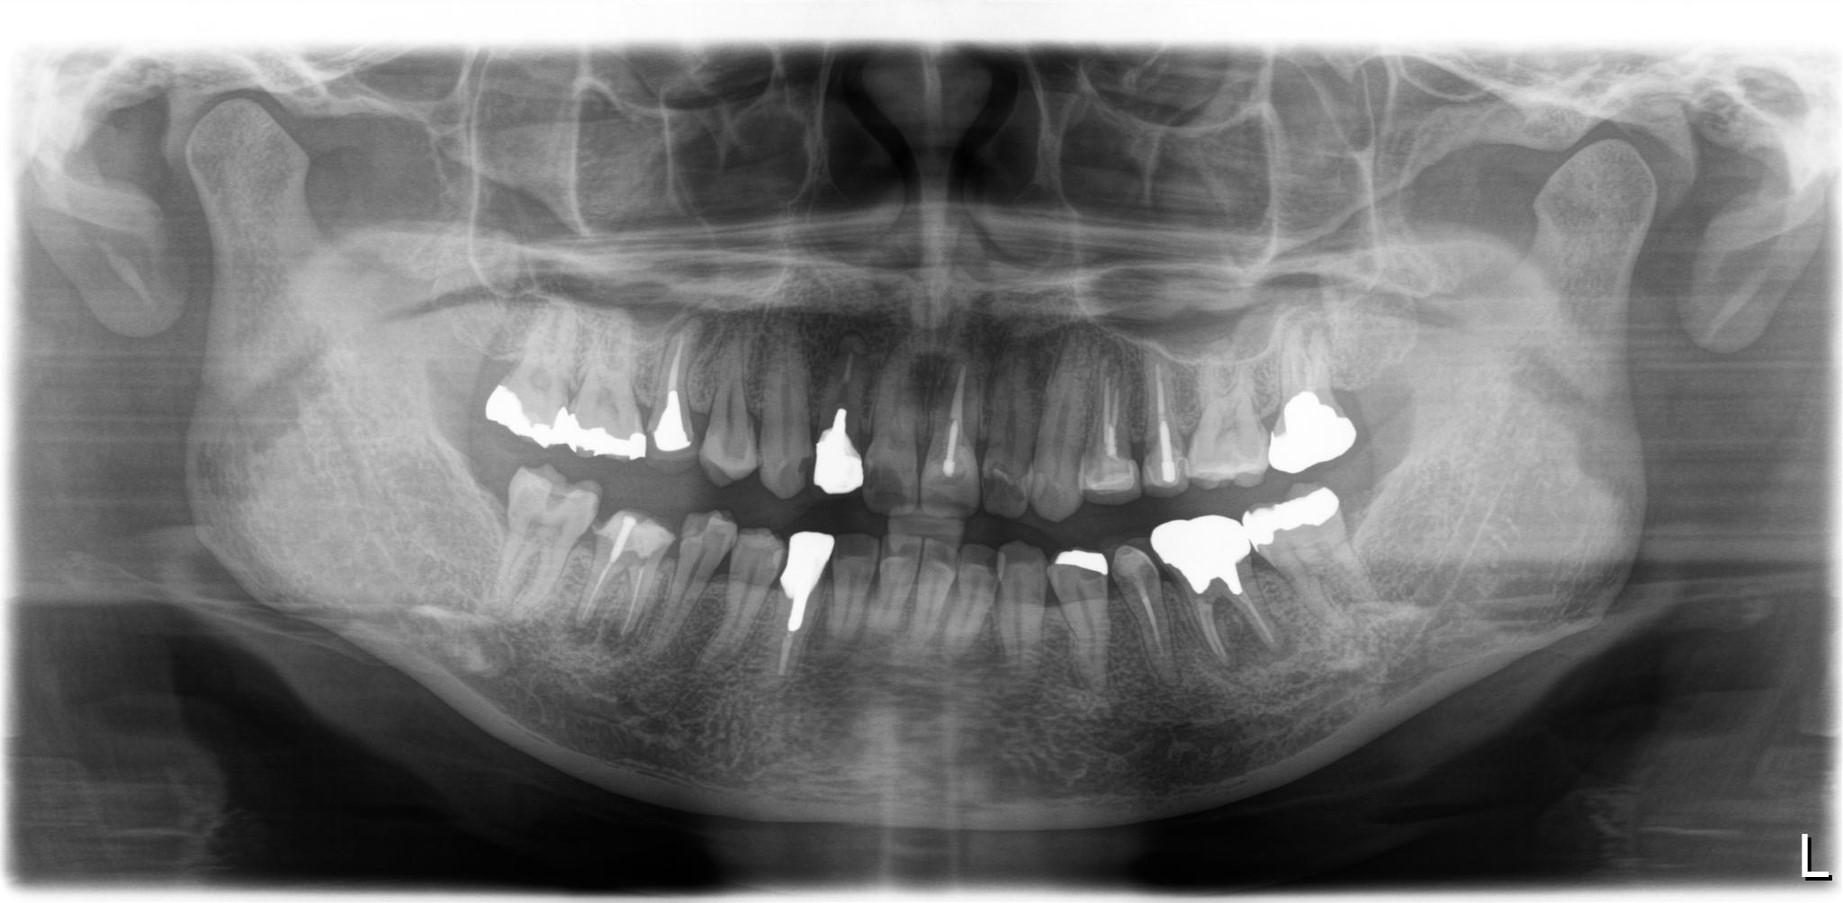

40代 男性

術前ですが左下6に大きな病変を認め膿がたまり抜歯が必要であるといわれ当院にお見えになりました。

根管治療術後2年です。膿の袋は綺麗に消失し被せ物が入り特に問題のない状態です。

費用 | 100000円 |

---|---|

治療期間 | 6か月 |

注意事項(リスク・副作用など) | 治療の刺激や薬剤の刺激により、治療後数時間から数日後に痛みや腫れが生じる場合があります。 |

カテゴリ | 歯内療法 |